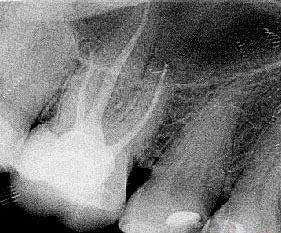

Примеры хорошо запломбированных каналов:

При лечении в одно посещение, зуб сразу восстанавливают пломбой. При лечении в два-три посещения полость зуба сначала закрывается временной пломбой, а в последнее посещение временную пломбу заменяют на постоянную.